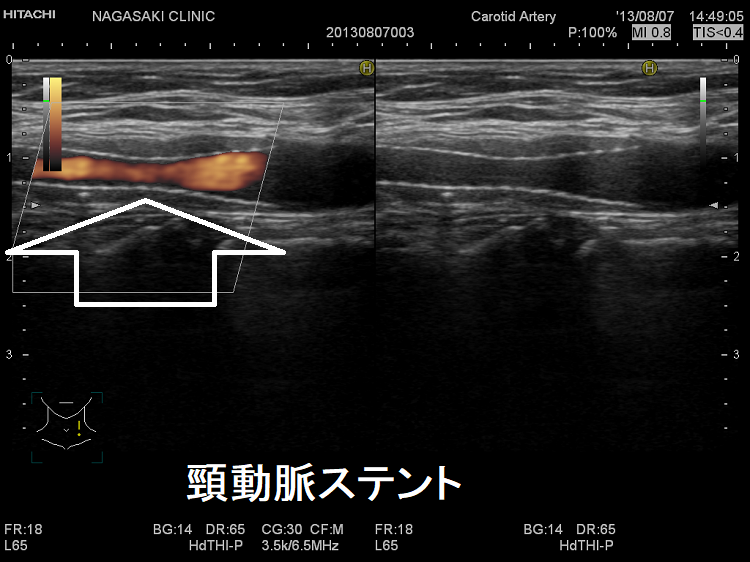

(↓)デジタルハイビジョン超音波装置で見たプラーク。

カテーテル手術、ステント留置

頸動脈ステントを留置した患者の甲状腺 超音波(エコー)画像;写真の頸動脈ステントを留置した患者は、甲状腺機能低下症/橋本病により動脈硬化が進行していました。(甲状腺と動脈硬化)